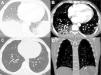

A 24-year-old man with sickle cell disease was admitted to our emergency department due to high fever (39.4°C) and bilateral pleuritic chest pain that had started 5 days previously. He had been admitted two times in the previous month due to pain crisis and respiratory symptoms. At that time, a chest X-ray showed a consolidation in the left lower lobe, and bacterial pneumonia was diagnosed. Pulmonary auscultation revealed decreased breath sounds over the lower lung fields. Laboratory tests showed mild leukocytosis (white cell count, 14,100/cm3) with 64% neutrophils, anemia (hemoglobin level, 7g/dl), thrombocytosis (790,000 platelets), and elevated C-reactive protein (98mg/L) and lactate dehydrogenase levels (482U/L). The patient underwent chest computed tomography (CT) angiography, which demonstrated bilateral pulmonary opacities associated with ground-glass attenuation over the lower lung fields (Fig. 1A) and mild pleural effusion on the right side. Pulmonary thromboembolism was ruled out (Fig. 1B). Two blood culture sets were negative and bronchoscopy was performed; cultures (bacterial and fungal) and GeneXpert results from bronchoalveolar lavage were negative. The patient was diagnosed with acute chest syndrome (ACS) and was treated successfully with blood transfusion, aggressive crystalloid hydration, analgesia, and antibiotic therapy with ampicillin plus sulbactam. His laboratory test values improved to normal and he was discharged from the hospital 7 days after initial treatment with an oral hydroxyurea prescription. One month after discharge, the patient underwent chest CT, which showed complete resolution of the pulmonary opacities (Fig. 1C). CT also showed characteristic findings of sickle cell disease, such as a small and calcified spleen and H-shaped vertebral bodies secondary to bone infarction of the central endplates (Fig. 1D). The final diagnosis of the condition leading to the patient's hospitalization was ACS.

(A) Chest CT image obtained with the lung window setting shows consolidations and ground-glass opacities in both lower lobes. (B) Angio-CT demonstrated no filling defect in the pulmonary arterial system. (C) Chest CT image obtained 1 month after discharge shows complete resolution of the pulmonary opacities. (D) Coronal reconstruction with the bone window setting demonstrates a small and calcified spleen (arrowheads) and H-shaped vertebral bodies with central endplate depressions (arrows).